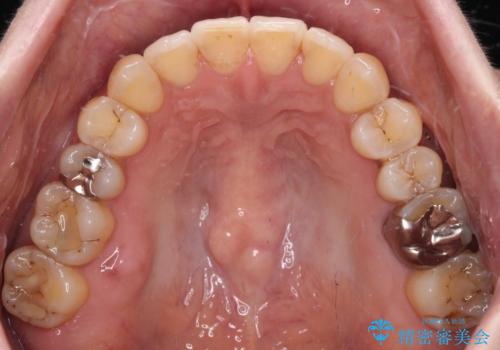

舌側転位している側切歯特有の、切縁の位置が不揃いであったり、根元が内側に引っ込んだ状態であったりという、インビザライン独特の仕上がりになることなく、きれいに整った歯列とすることができました。